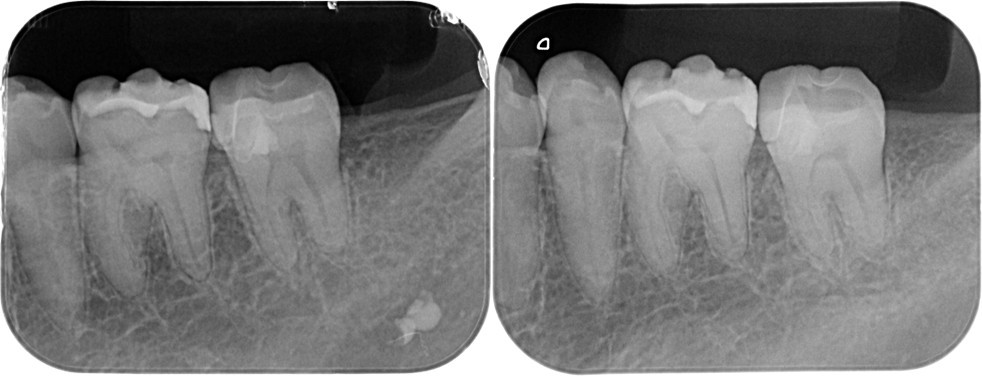

(図14)VPT症例

露髄面の大きさは関係なく正常な歯髄が存在し、健全象牙質上にMTAのセメント層が3ミリ確保できれば良好な結果が得られる

(図15)術後5年経過

髄角付近にデンティンブリッジ形成による硬組織の生成が確認できる

左:2017.07.31 中:2017.07.31 右:2018.10.15

左:2018.10.29 中:2018.11.02 右:2019.02.14

左:2021.08.27 中:2021.08.27 右:2022.03.23